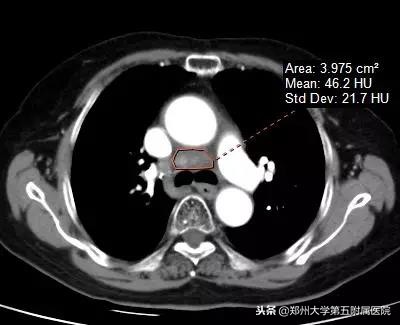

▲ 纵膈占位伽玛刀治疗前和伽玛刀治疗后对比,肿块明显缩小,压迫症状好转